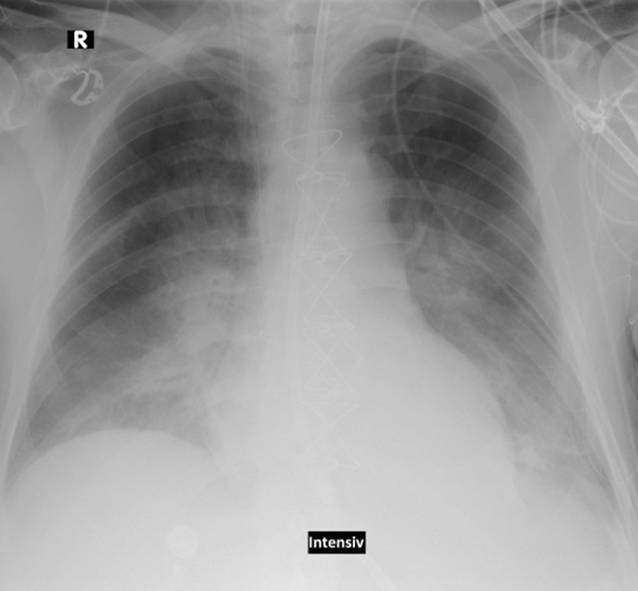

Um Lungenstauung zu diagnostizieren, kann der Arzt verschiedene Tests durchführen. Dazu gehören eine körperliche Untersuchung, eine Röntgenaufnahme der Brust, eine Echokardiographie zur Überprüfung der Herzfunktion und eine Blutuntersuchung, um mögliche Ursachen zu identifizieren.

Die Diagnose der Lungenstauung bei Kindern erfolgt in der Regel durch eine gründliche körperliche Untersuchung, eine Anamneseerhebung und verschiedene diagnostische Tests. Dazu gehören Röntgenaufnahmen der Brust, EKGs (Elektrokardiogramme) und Echokardiogramme, um die Struktur und Funktion des Herzens zu beurteilen.

Die Diagnose von Lungenstauung wird in der Regel durch eine gründliche körperliche Untersuchung, eine Anamnese des Patienten und verschiedene medizinische Tests gestellt. Dazu können Röntgenaufnahmen der Lunge, Echokardiographie, Computertomographie (CT) oder Magnetresonanztomographie (MRT) gehören. - Ist Lungenstauung heilbar?